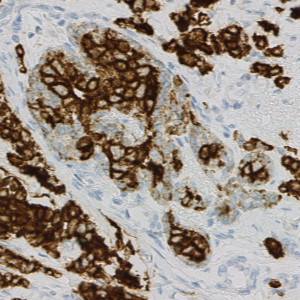

Figure 1

CK slide.